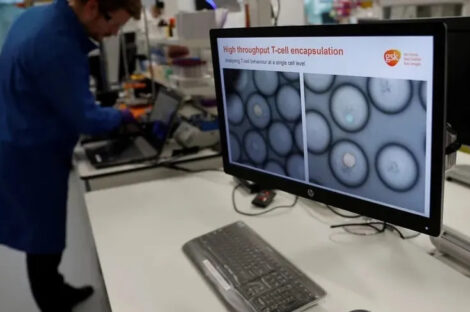

تطور طبي يوصف بالاختراق الثوري، حيث أعلن باحثون من جامعة رايس في تكساس عن تطوير علاج جديد للسرطان يعتمد على…

كشفت دراسة حديثة أجراها مركز أبحاث السرطان في جامعة فيينا الطبية عن اختراق علمي محتمل قد يغيّر جذرياً الطريقة التي…

شهد المجال الطبي تطورًا ملحوظًا مع الإعلان عن علاج مناعي مبتكر لمرضى سرطان الرأس والرقبة، والذي أظهر نتائج واعدة في…